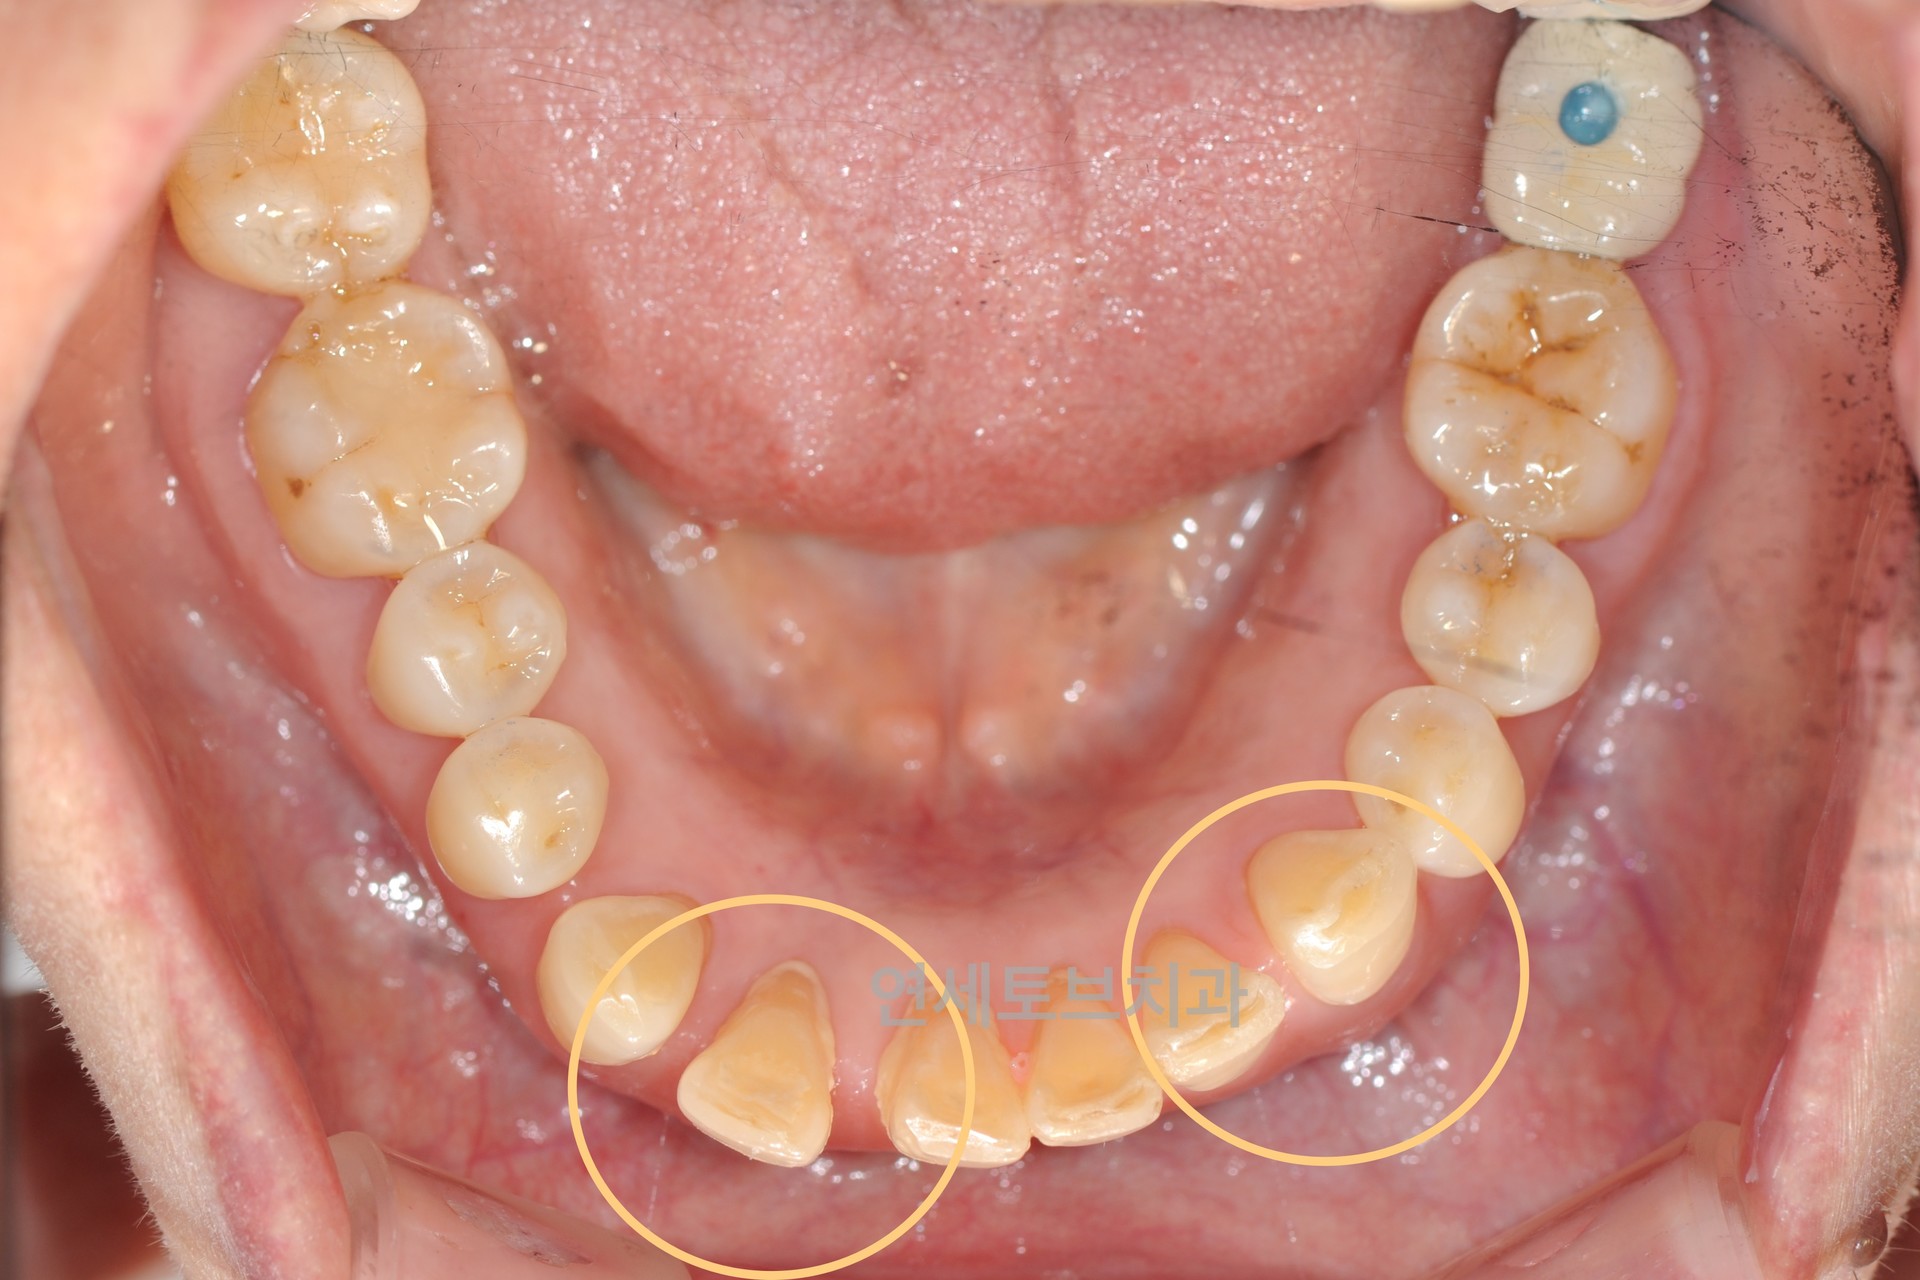

중장년층(40대 이상)에서 앞니 부분 교정은 주로 나이가 들면서 앞니 배열이 흐트러지거나 치아 사이에 공간이 생기는 문제를 해결하는 치료입니다.

젊었을 때는 가지런했던 앞니가 나이가 들수록 점점 삐뚤어지거나, 잇몸 질환 등으로 인해 치아가 이동하는 현상이 흔하게 나타납니다.

Before